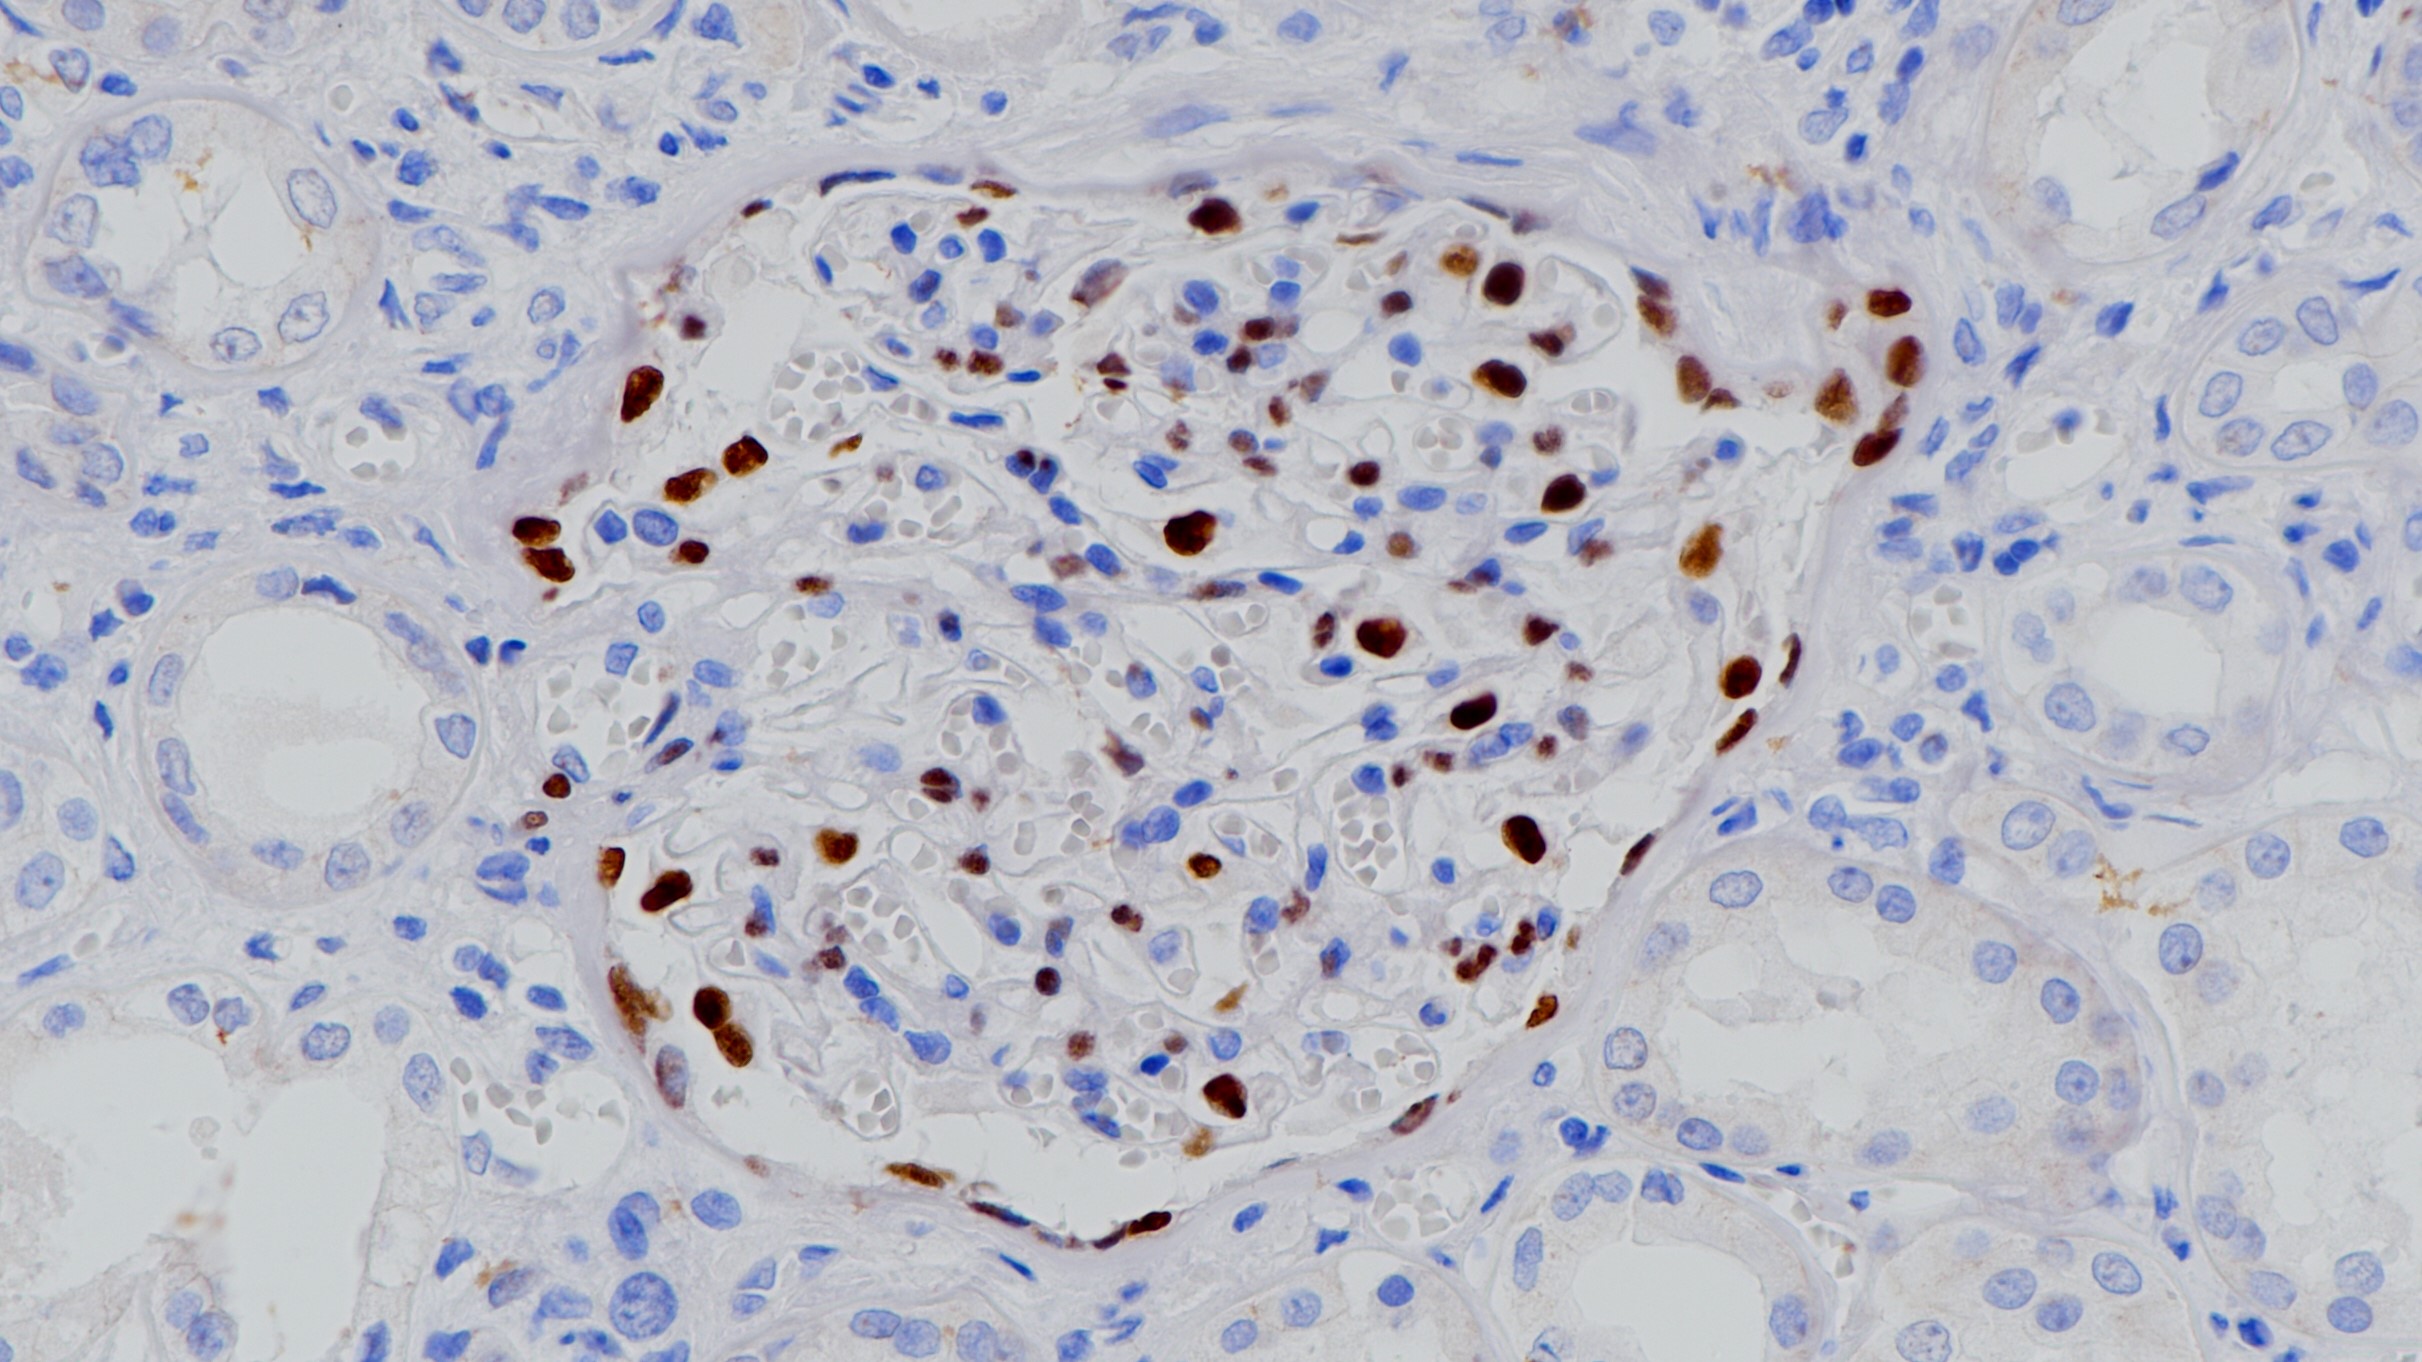

WT1作为转录因子,在泌尿生殖系统的发育过程中起到重要作用。正常上皮细胞中,WT1主要在输卵管和卵巢表面的上皮细胞表达,而在子宫内膜和宫颈的上皮细胞不表达。非上皮细胞中,WT1在间皮基质细胞、女性生殖道的基质细胞、睾丸的非生殖细胞以及肾脏的足细胞中表达。肿瘤组织中,WT1主要在Wilm’s瘤和间皮瘤中表达,浆液性卵巢癌和一些乳腺癌中也有表达,在临床上可用来鉴别恶性间皮瘤和浆液性卵巢癌。

细胞核

卵巢癌